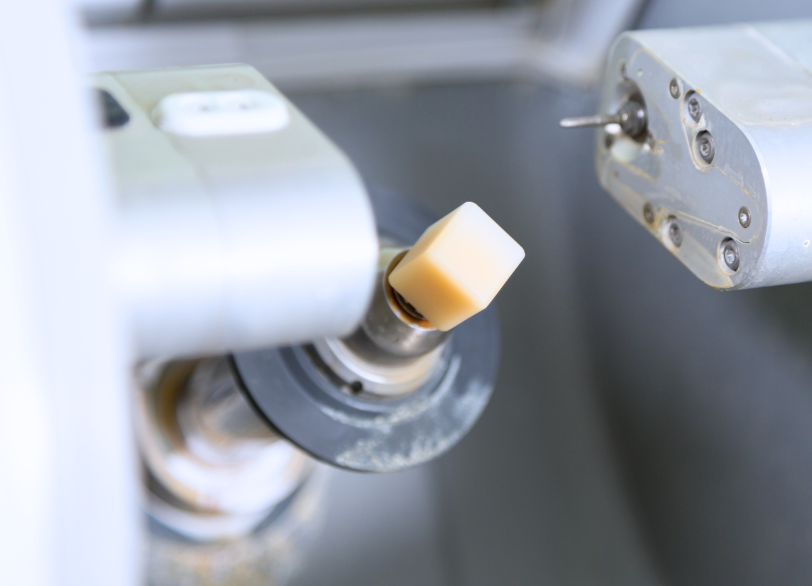

セレックブロック(規格生産セラミック)

セレックシステムで使用するのは、これらのジルコニアやガラスセラミックを、厳しい品質管理のもとで工場生産された「セラミックブロック」です。 歯科医院や歯科技工所で、粉から手作業で製作するセラミックと異なり、素材の内部に気泡などが一切なく、均質で、極めて高い強度と安定性を誇ります。 どの修復物も、常に高い品質が保証されていること。それが、セレック治療の信頼性の高さを支えています。